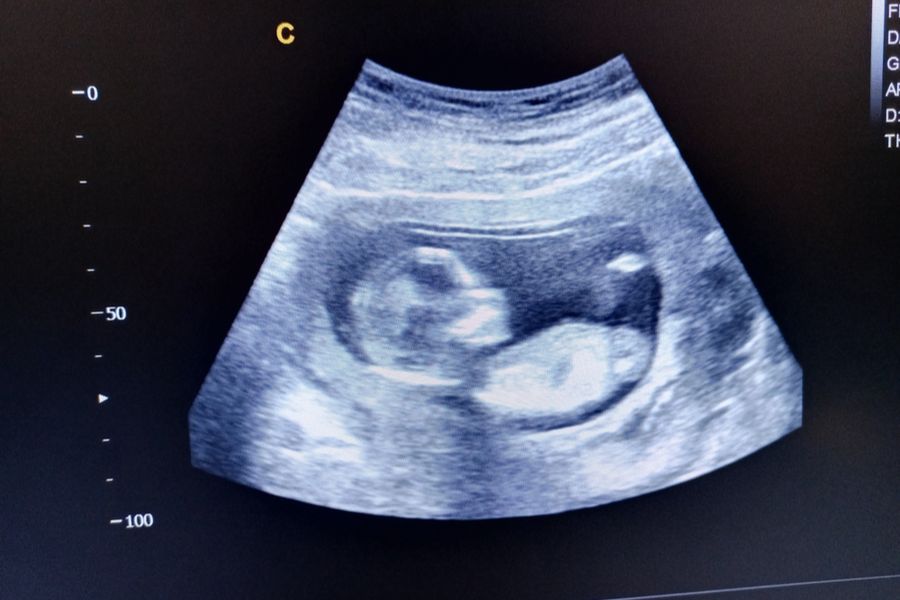

Current laws in Virginia allow abortion up to the end of the 26th week of pregnancy, which is one of the most permissive policies in the country. In 2020, former Gov. Ralph Northam signed bills that ended a 24-hour waiting period for abortions and the mandatory pre-abortion ultrasound, which had been law for decades.

Following the U.S. Supreme Court overturning Roe v. Wade, the newly elected Youngkin sought to work with lawmakers to establish some limits on abortion, but all efforts were stifled in Senate committees. This included a proposed 15-week ban and a proposed ban at the point of viability, which all Education and Health Committee Democrats opposed. Republican Sen. Siobhan Dunnavant also opposed the 15-week ban but supported the ban at the point of viability, which occurs around 24 weeks of pregnancy.